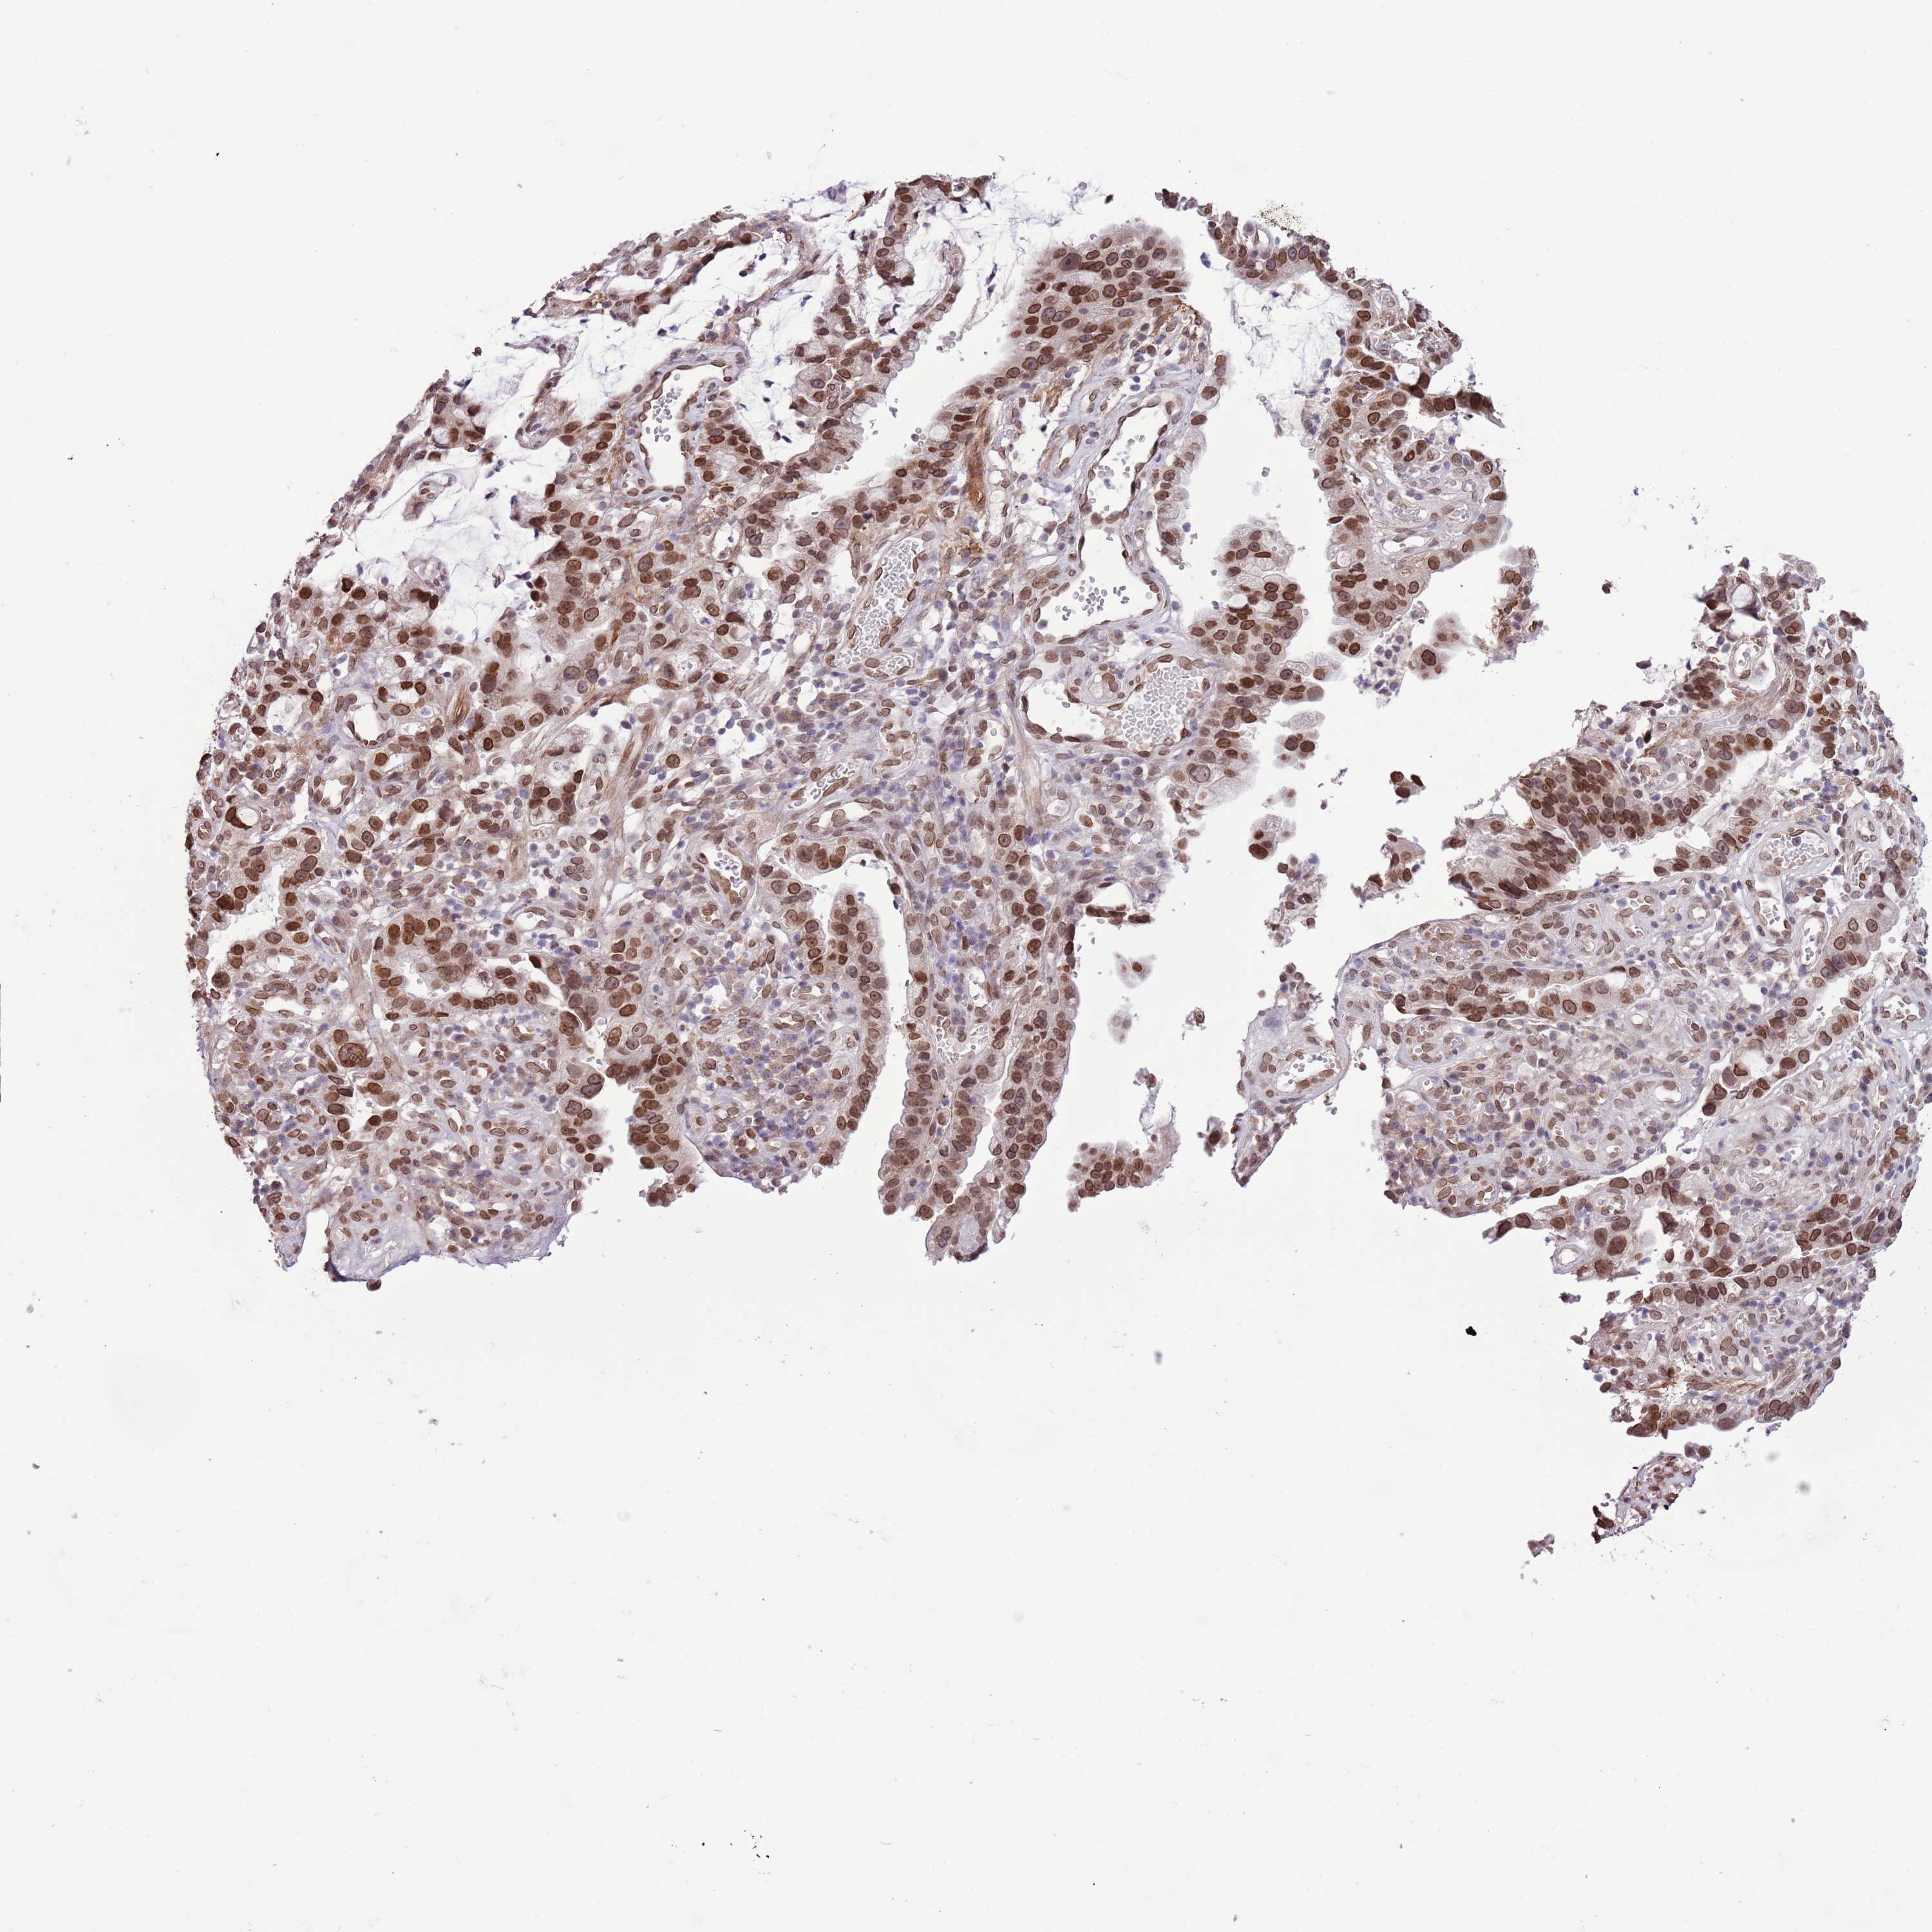

STOMACH CANCER - Protein expressioni

A mouse-over function shows sample information and annotation data. Click on an image to view it in a full screen mode. Samples can be filtered based on level of antibody staining by selecting one or several of the following categories: high, medium, low and not detected. The assay and annotation is described here.

Note that samples used for immunohistochemistry by the Human Protein Atlas do not correspond to samples in the TCGA dataset.

Antibody stainingi

Antibody staining in the annotated cell types in the current human tissue is reported as not detected, low, medium, or high, based on conventional immunohistochemistry profiling in selected tissues. This score is based on the combination of the staining intensity and fraction of stained cells.

Each image is clickable and will lead to virtual microscopy that enables deeper exploration of all samples and also displays staining intensity scores, fraction scores and subcellular localization as well as patient and tissue information for each sample.

Antibody HPA049855

Staining

High

Medium

Low

Not detected

Intensity

Strong

Moderate

Weak

Negative

Quantity

>75%

75%-25%

<25%

None

Location

Nuclear

Cytoplasmic/membranous

Cytoplasmic/membranous,nuclear

Adenocarcinoma, NOS